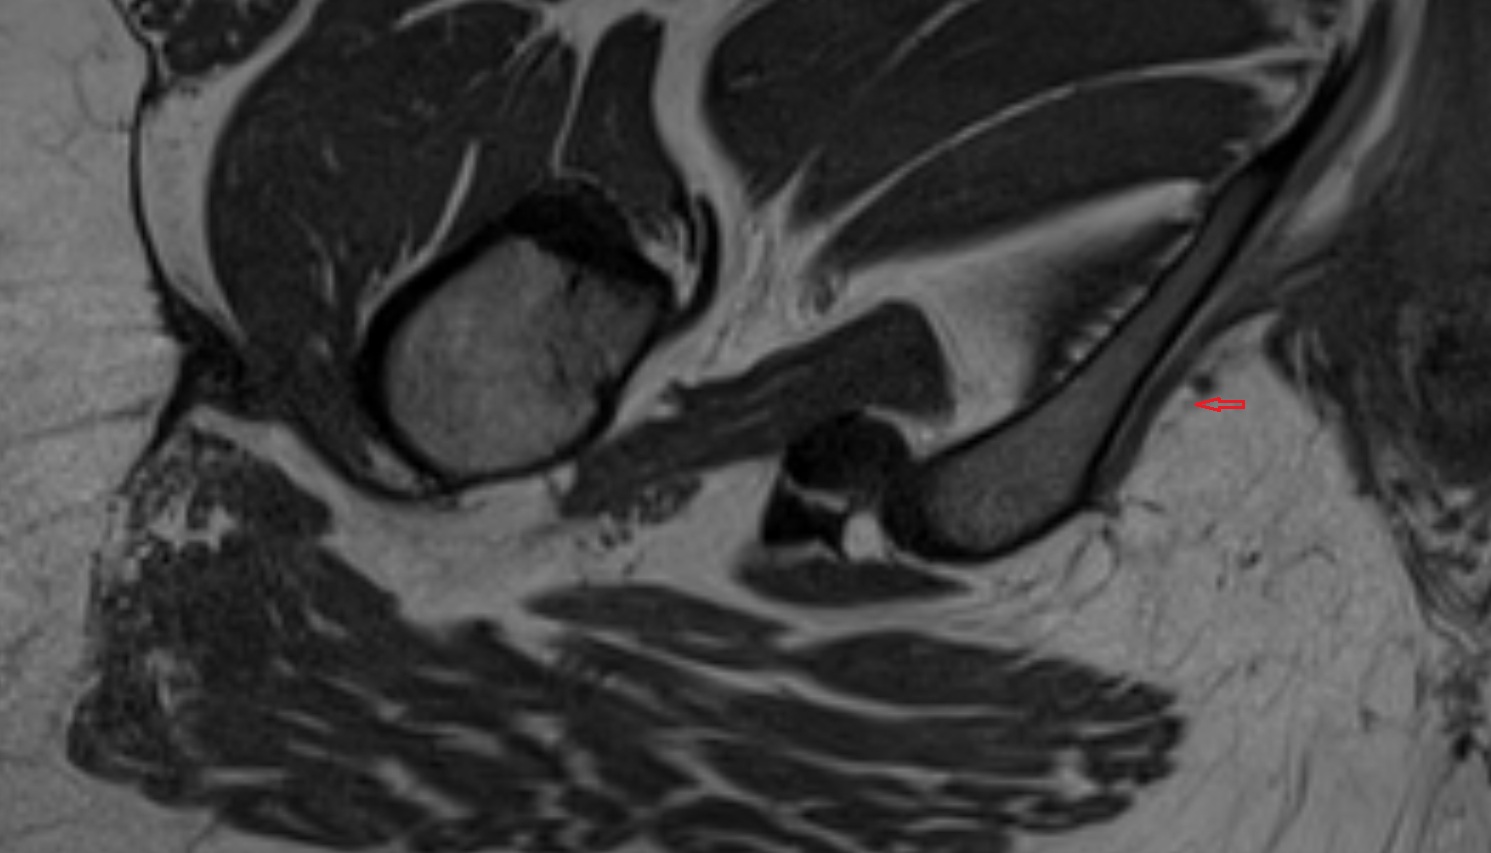

- Hip joint